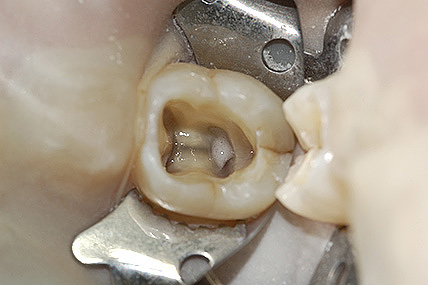

La prima fase della terapia è la corretta esecuzione di una radiografia diagnostica/preoperatoria al fine di ottenere tutte le informazioni sull’anatomia del dente in esame, successivamente si deve isolare il dente con la diga di gomma; è questo un presidio indispensabile per l’esecuzione di una corretta terapia il cui obiettivo è quello di disinfettare e detergere un sistema canalare (endodonto), e dunque il primo passo da fare è quello di evitare di contaminarlo ulteriormente con i batteri di cui la saliva è ricca. Il dente isolato con la diga di gomma è infatti completamente separato dal resto della bocca, garantendo un’ottimale detersione chimica da un lato e preservando il paziente dalla involontaria ingestione di disinfettanti o strumentario.

Dopo aver isolato il dente si inizia a rimuovere l’otturazione o la corona del dente da trattare e si esegue una corretta apertura della camera pulpare, al fine di ottenere un accesso diretto al sistema dei canali radicolari.